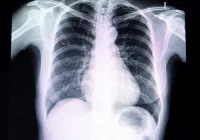

The study involved adults attending the Yorkshire Lung Screening Trial (YLST), which offered LDCT screening as part of a community-based "Lung Health Check" (LHC) in Leeds, UK. YLST aimed to implement lung cancer screening as a routine NHS service without explicitly stating its research nature in initial communications. Eligibility for screening was based on specific criteria, including age, smoking history, and lung cancer risk models. Participants who consented to screening underwent LDCT scans at mobile units located in community-based settings. Smoking cessation services were offered to those who smoked or had elevated carbon monoxide levels, with opt-out provision by co-located smoking cessation practitioners (SCPs). Demographic, clinical, and smoking-related data were collected for all participants.

The study focuses on the uptake and 4-week quit rates of a smoking cessation service co-located with a community-based LDCT lung cancer screening program. Among eligible participants, 89% agreed to immediate consultation with a smoking cessation practitioner (SCP), and three-quarters accepted longer-term support, indicating high acceptance of the cessation service. About 15% of eligible participants reported abstinence from smoking at the 4-week mark, highlighting the potential life-saving impact of integrating smoking interventions into screening programs. The study cohort comprised predominantly individuals from deprived populations with low educational attainment and was mostly of White ethnicity. Most participants initiated smoking during adolescence, displayed low motivation to quit, and had made few quit attempts in the past year. However, higher motivation to stop smoking, self-efficacy of quitting, and nicotine dependency were associated with greater uptake of cessation support.